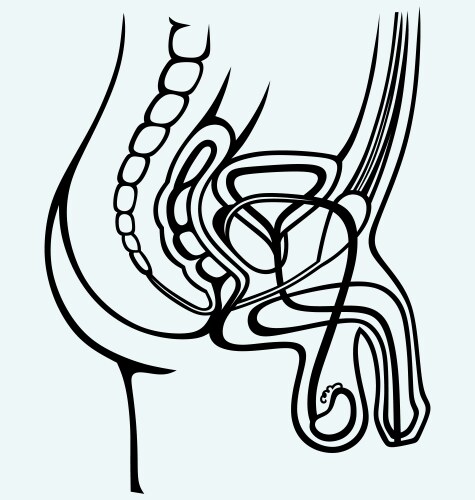

- Anatomy

- Reproductive

- Biological

- Biology

- Body

- Physiology

- Urology